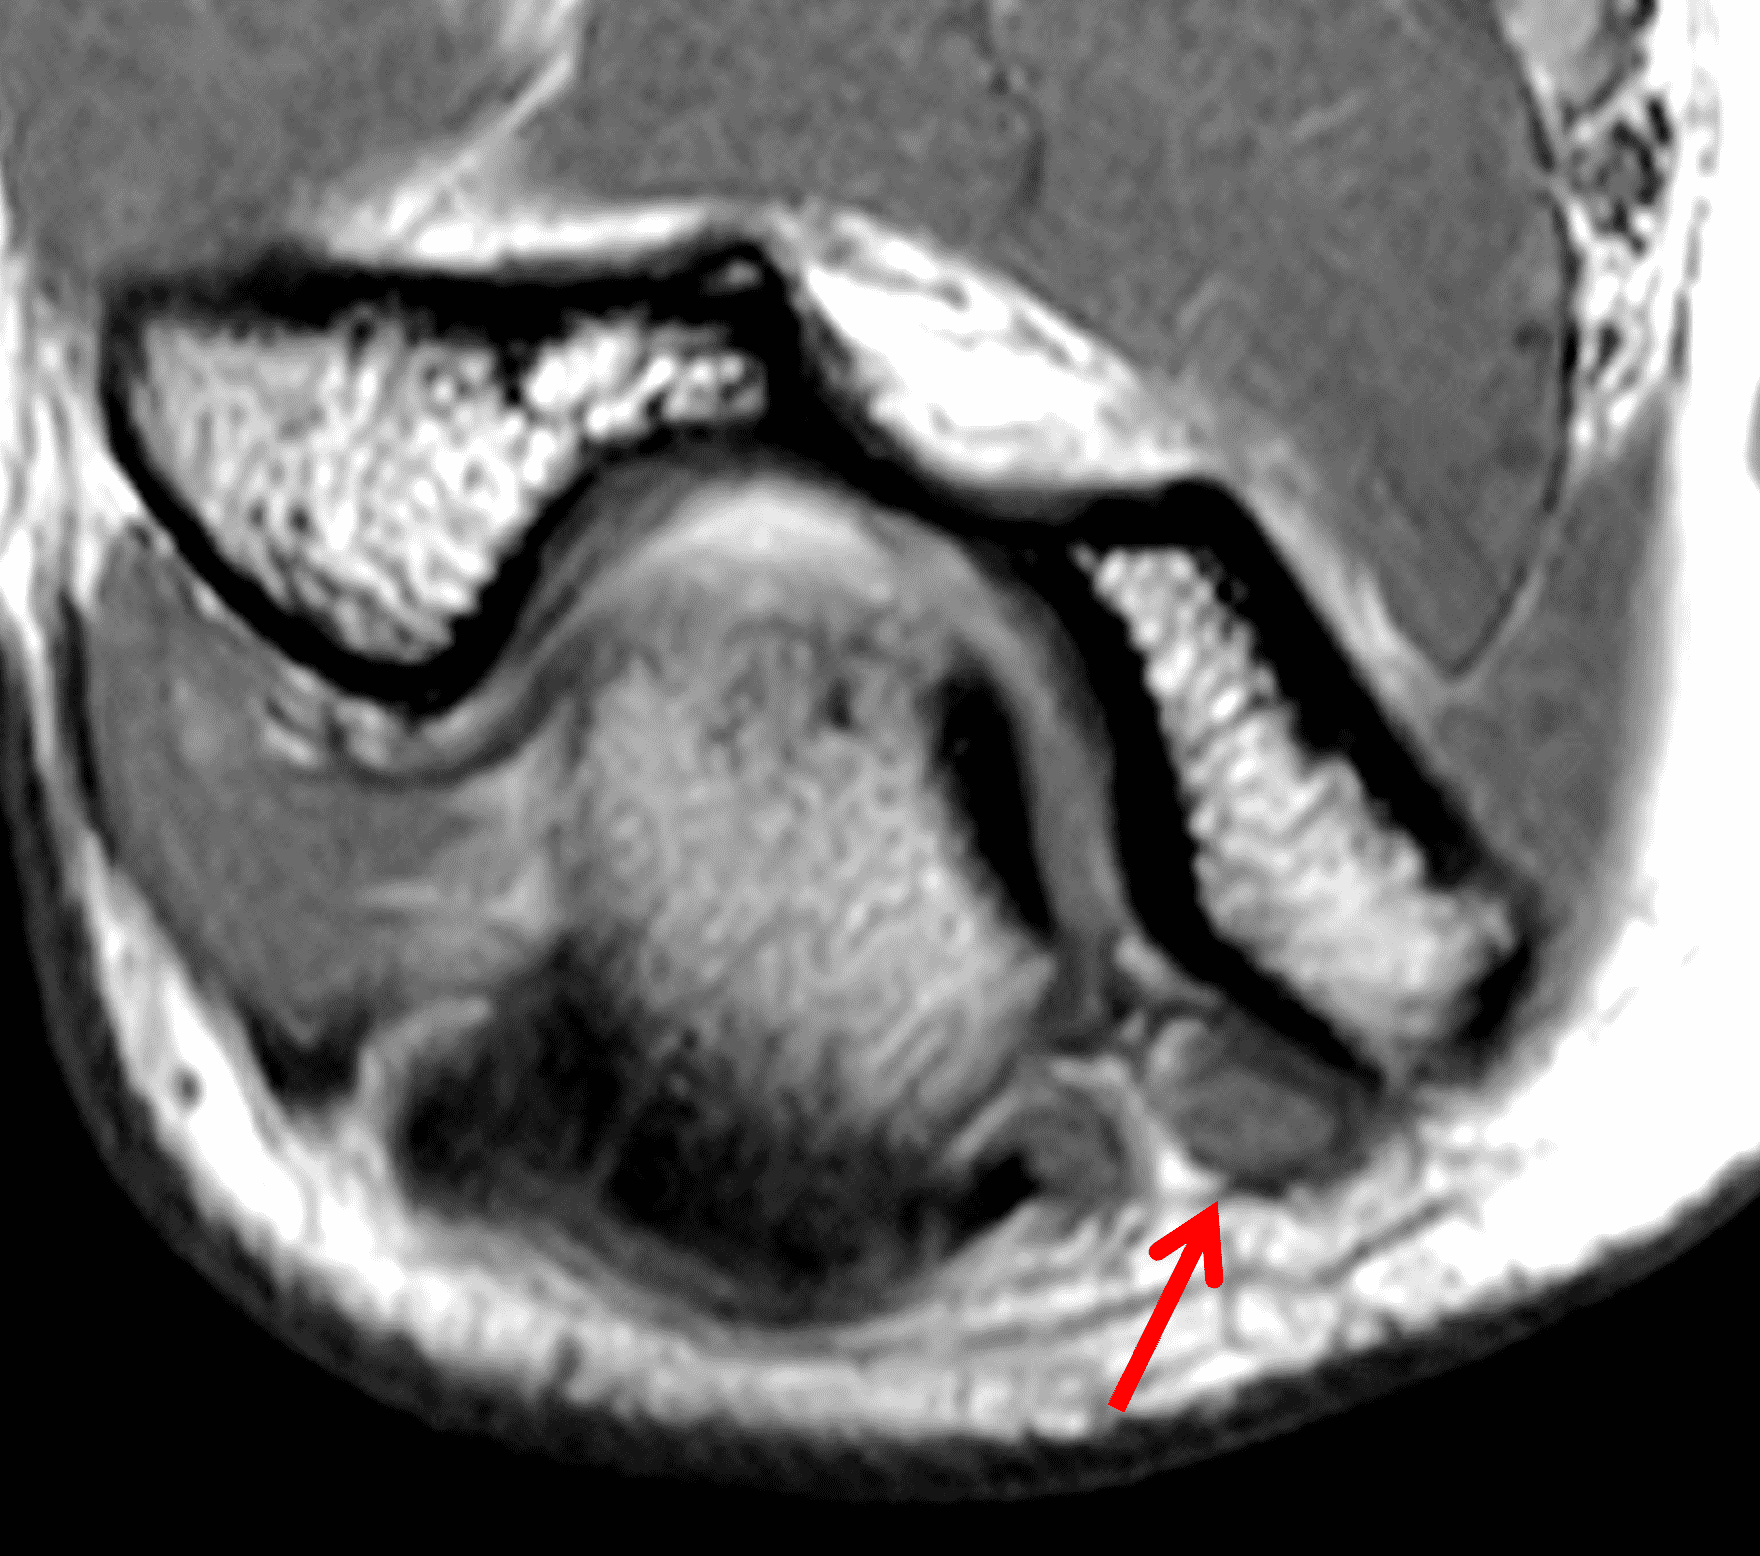

Figure 2: At the level of the cubital tunnel (2A and 2C), identifiable by the thin cubital tunnel retinaculum (yellow arrow), the ulnar nerve (red arrow) is focally enlarged and hyperintense compared to the nerve more distally (2B and 2D), where it lies between the two heads of the flexor carpi ulnaris muscle (asterisks). No soft tissue mass is present.